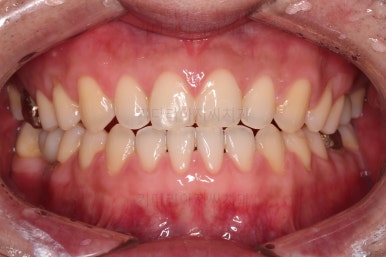

초진 시의 입안 모습입니다.

어금니가 빠져서 결손치아가 있고 치아 사이에 틈새도 있어서 교정치료도 함께 원한다고 내원해 주셨어요.

사진에서 보시는 바와 같이 윗니 1개, 아랫니 1개의 결손 부위가 보입니다.

윗니 어금니 중에는 신경치료를 마무리 못하고 임시재료로 메꿔뒀던 부위도 보이고요.

환자분 : "원래 틈새가 없었는데 점점 치아 사이가 벌어져요."

전후 사진을 비교해 볼게요.